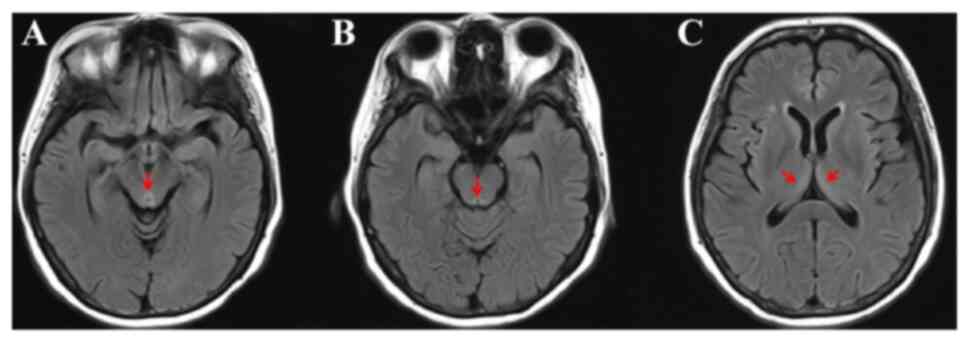

Figure 3.

Brain magnetic resonance imaging. (A) T2 FLAIR imaging showing hyperintensity in the periaqueductal midbrain (arrow). (B) T2 FLAIR imaging showing hyperintensity in the periaqueductal gray matter (arrow). (C) T2 FLAIR imaging showing hyperintensity in the thalami (arrow). FLAIR, fluid-attenuated inversion recovery.

By August, the patient had lost ~4.6 kg, which represented a loss of 5–7.5% of total body weight occurring in <2 months, and they now returned to the hospital due to the spontaneous rupture of a mass in the right lower abdomen. Based on the Malnutrition Universal Screening Tool assessment (Fig. 1), the patient was considered to be at high risk of malnutrition (score 3) due to substantial weight loss and the current acute disease status, despite having a body mass index of 23.03 (10). A computed tomography scan confirmed that the primary cervical cancer had spread to the right lower abdomen and broken through the skin (Fig. 2). The wound, with significant exudate, was cleaned twice daily, and the patient continued to receive TPN due to poor oral intake. At 10 days after admission, the patient exhibited sudden cognitive impairment, especially in recent and immediate memory. An examination performed by a neurologist showed that she was conscious but disoriented with regard to time, place and person. The Mini-Mental State Exam (MMSE) and Montreal Cognitive Assessment (MoCA) scores were 19/30 and 17/30, respectively (11,12). In addition, ophthalmoplegia with bilateral sustained nystagmus was observed. Eye movement was normal to the left side, but abnormal to the right side. The patient could not walk due to cancer metastases within the right iliopsoas muscle and iliac wing. Consequently, a gait assessment was not performed. Mild upper-limb ataxia was observed and tendon reflexes exhibited a slight response. All other neurological examinations, including assessments of muscle tone and strength, were normal. Brain MRI and magnetic resonance angiography (MRA) were performed immediately. The MRA demonstrated normal blood vessels without restricted diffusion, which excluded the possibility of ischemic or hemorrhagic stroke. No significant abnormalities were detected on T1-weighted imaging and diffusion-weighted imaging, which further ruled out the possibility of brain metastases. However, brain MRI demonstrated hyperintensity in the periaqueductal midbrain on T2 fluid-attenuated inversion recovery imaging (Fig. 3). The patient's laboratory results were as follows: White blood cell count, 6.34×109/l (normal range, 3.5–9.5×109/l); red blood cell count, 3.69×1012/l (normal range, 4.3–5.8×10¹2/l); hemoglobin, 86 g/l (normal range, 120–160 g/l); platelets, 277×109/l (normal range, 125–350×109/l); alanine aminotransferase, 14.4 U/l (normal range, 7–40 U/l); aspartate aminotransferase, 15.9 U/l (normal range, 13–35 U/l); serum albumin, 32.62 g/dl (normal range, 40–55 g/l); potassium, 4.88 mmol/l (normal range, 3.5–5.3 mmol/l); magnesium, 0.90 mmol/l (normal range, 0.77–1.03 mmol/l); folate, 5.3 ng/ml (normal range, 3.38–5.38 ng/ml); and vitamin b12, 605 pg/ml (normal range, 211–911 pg/ml). Serum thiamine levels were not tested due to laboratory constraints. Several other conditions, including brain metastases, acute cerebrovascular disease and electrolyte imbalance, were considered and excluded based on clinical symptoms, imaging examination and laboratory results. Furthermore, the TPN regimen did not include routine thiamine supplementation, which may have promoted the development of WE. Thiamine (100 mg) was immediately administered intramuscularly three times a day. After 1 week of treatment, the patient's eye movement disorder and recent memory improved, with the MMSE and MoCA scores changing to 23/30 and 20/30, respectively. The patient was subsequently discharged and returned to her hometown. After 3 months, a telephone follow-up was conducted. It was noted that the patient showed rapid progression of the primary tumor, along with ongoing partial recent memory impairment and spatial disorientation. Ultimately, the patient passed away due to complications related to the tumor. The timeline of the disease course is presented in Fig. 4.